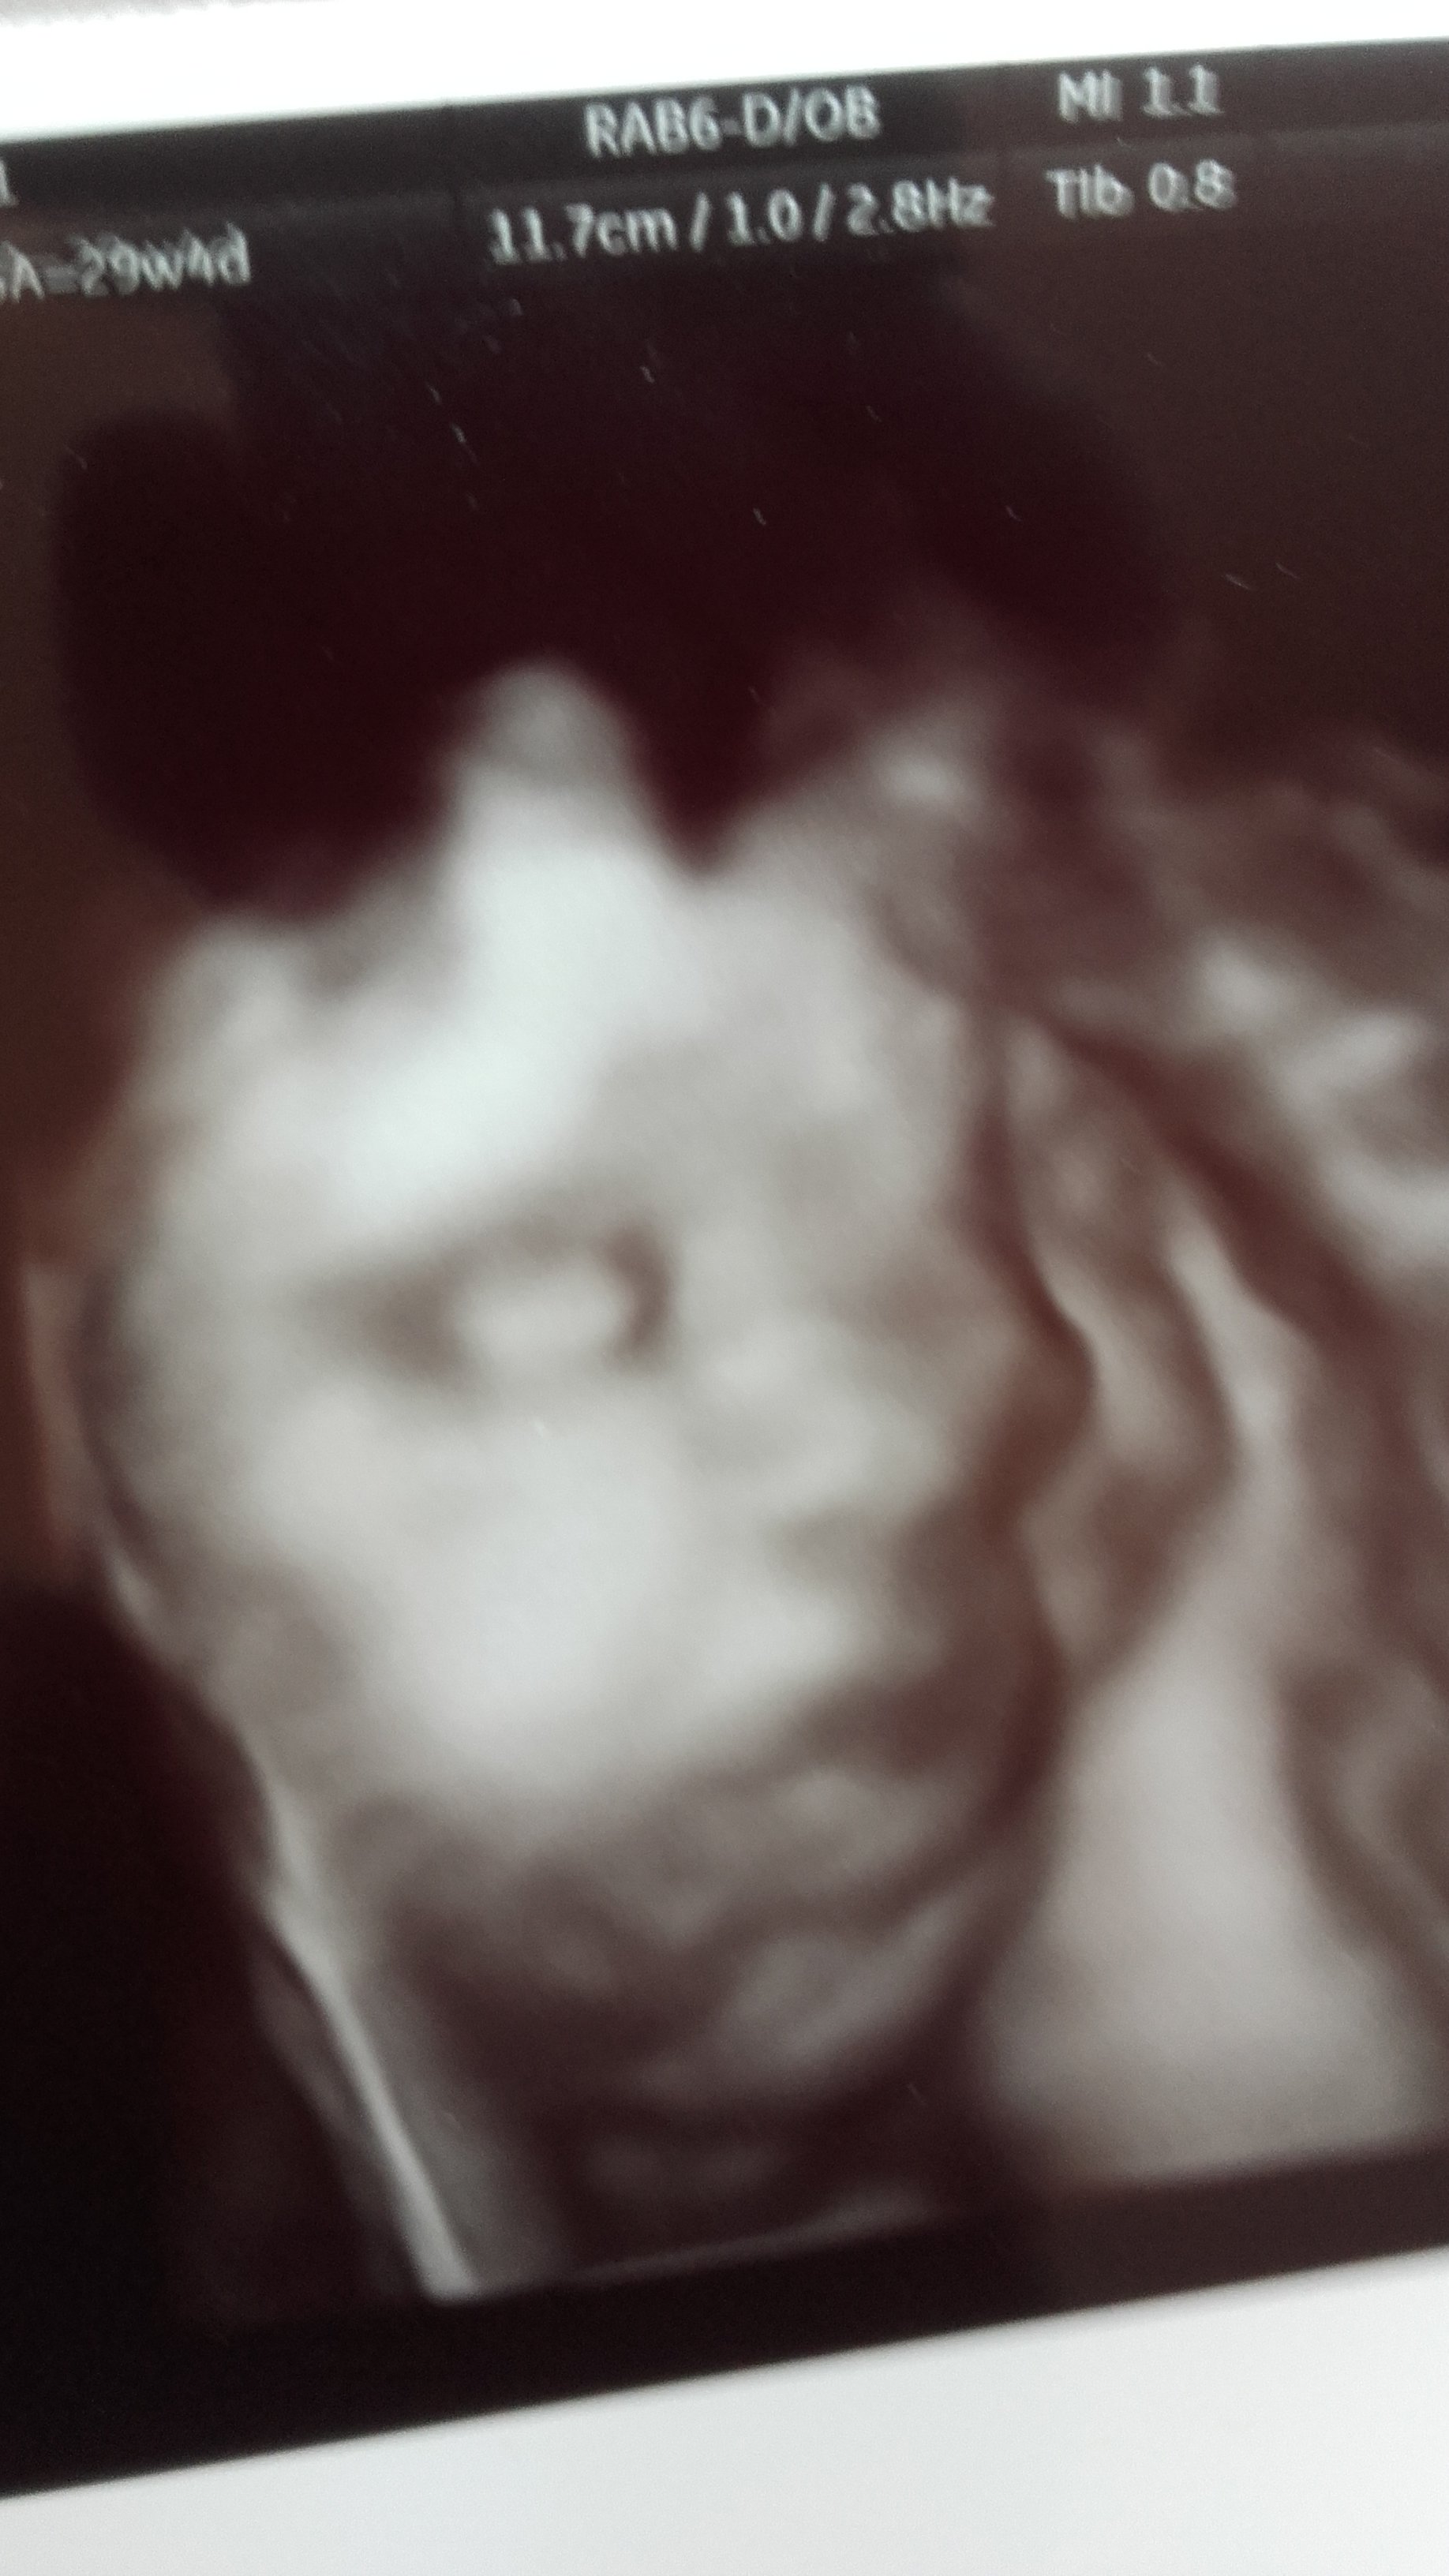

Chciałam jednak podzielić się z Wami zdjęciem twarzyczki mojej coruni . Rozpływam się nad nim.

Zobacz załącznik 862082